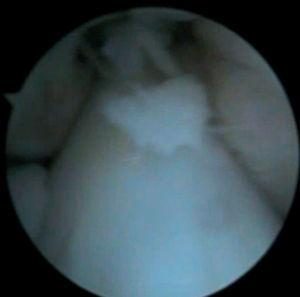

Figura 6 Artroscòpia. Cossos lliures al voltant dels lligaments encreuats i en altres localitzacions intraarticulars.

Figura 7 Artroscòpia. Cossos lliures al voltant del lligament encreuat íntegre.

Figura 8 Artroscòpia. Cossos lliures al voltant del lligament encreuat íntegre.

Es practica una artroscòpia, en la qual s'observen (figs. 2, 4, 6-8):

• Múltiples fragments condrals lliures de vores agudes, que s'identifiquen com recents, i de vores rodones que es cataloguen com antics.

• Resta d'estructures intraarticulars íntegres.

• Es procedeix a l'exèresi dels cossos lliures i la regularització de la lesió condral seguida d'estabilització per vaporització.